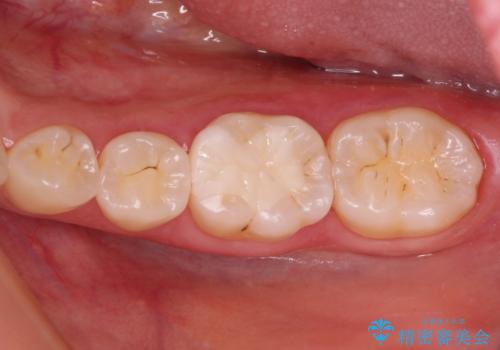

丈夫なクラウンを装着できただけでなく、形態や色調も自然に仕上げることができました。